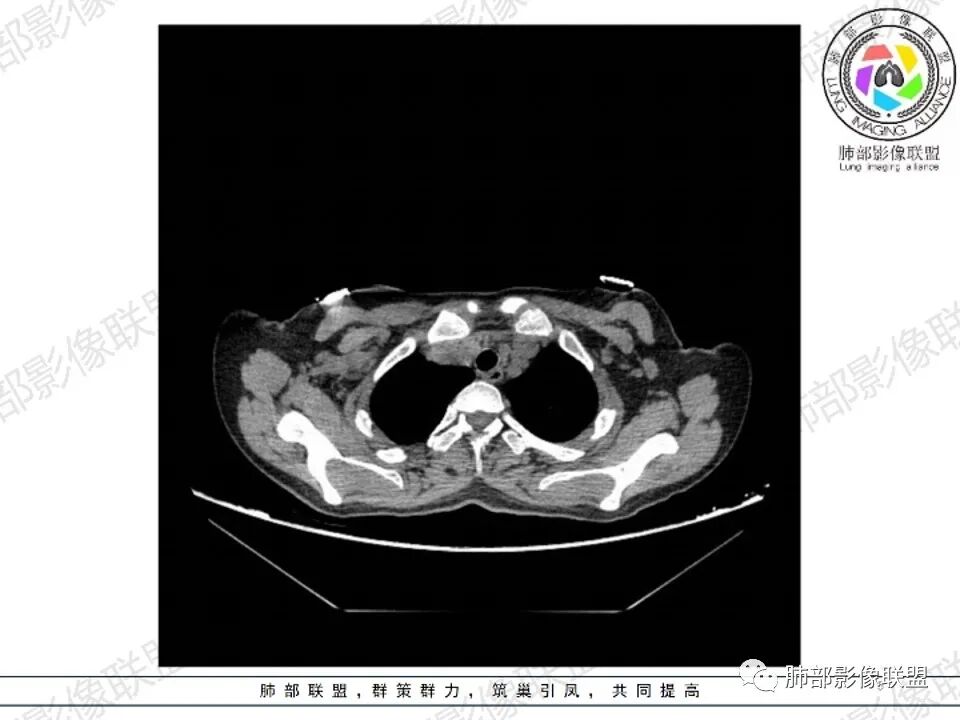

4.双侧腋窝区见增大淋巴结,边界清楚。

1.年轻女性,前纵隔不规则块状影,密度不均,边界不甚清楚,有结节融合感,轻度不均匀强化,可见血管穿行,最常见最符合的无疑是淋巴瘤!